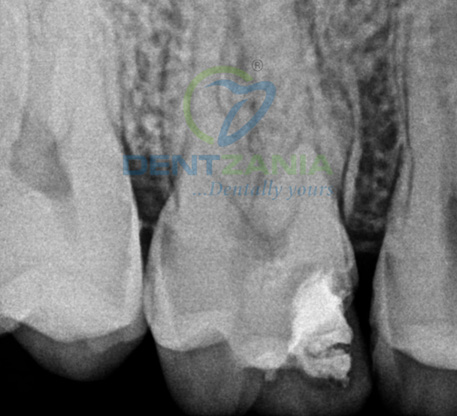

1. Diagnosis & X-Ray

X-rays are taken to assess the damage

- Decay has reached the tooth pulp (the living tissue inside the tooth).

- Infection or abscesses have developed at the root tip or inside the tooth.

- Injury or trauma to the tooth.

- The presence of an abscess (or pimple) on the gums.

- Sensitivity to hot and cold temperatures.

- Severe toothache.

- Swelling and/or tenderness.